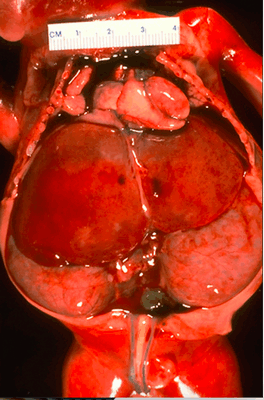

Рисунок 1 | Плод, 23 недели. Смерть плода после преждевременных родов наступила из-за гипоплазии легких, причиной которой является маловодие вследствие ПБП.

Увеличение обеих почек со смещением органов брюшной полости в сочетании с гипоплазией легкого.